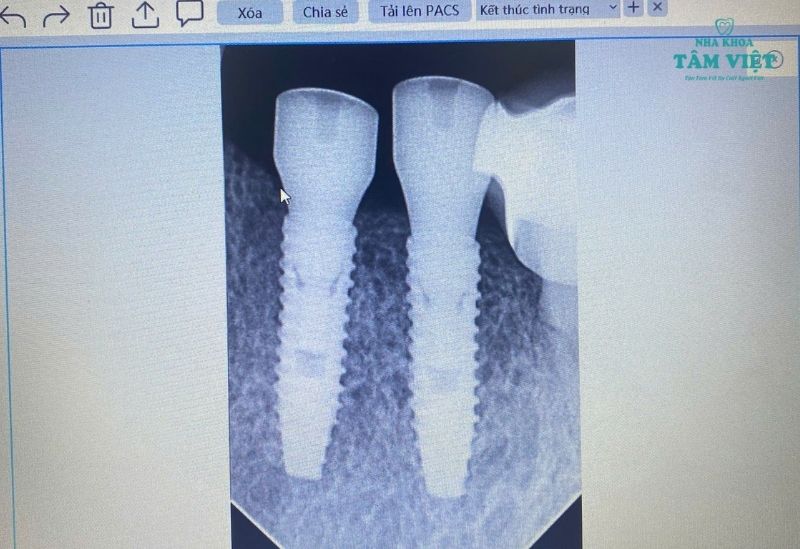

Đội ngũ bác sĩ của chúng tôi giàu kinh nghiệm, chuyên sâu về cấy ghép Implant và đã thực hiện thành công hàng ngàn ca phức tạp. Toàn bộ quy trình được hỗ trợ bởi hệ thống trang thiết bị hiện đại như máy chụp phim CT Cone Beam 3D, đảm bảo an toàn và chính xác tuyệt đối. Chúng tôi cung cấp đa dạng các loại trụ Implant chính hãng từ Hàn Quốc, Mỹ, Thụy Sĩ, giúp bạn có nhiều lựa chọn phù hợp.